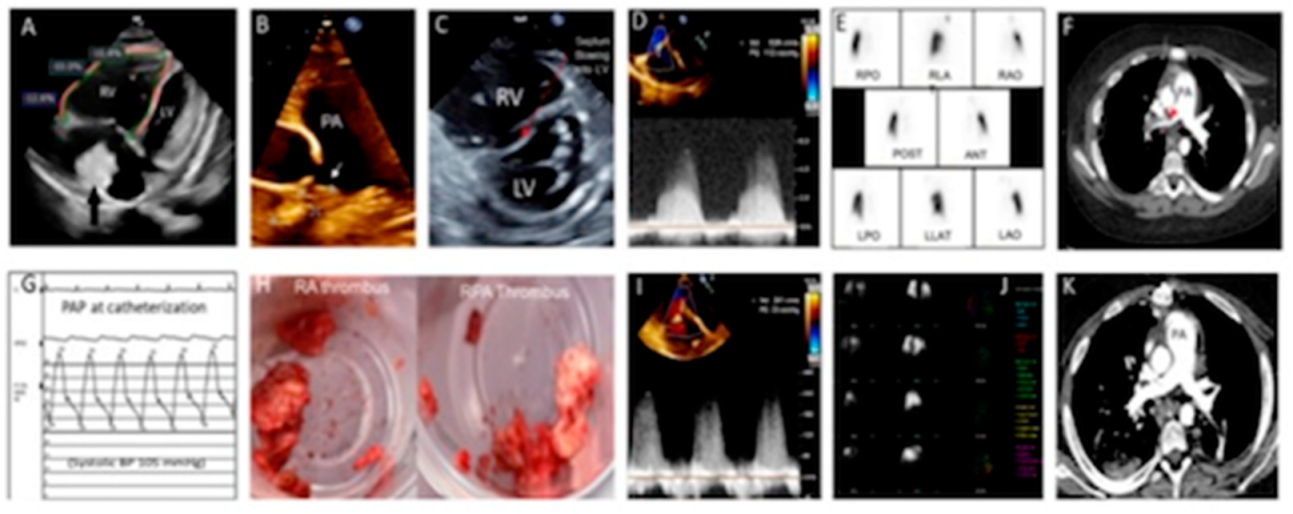

His echocardiogram revealed thrombi in the right atrium (RA) (Figure 2A) and right pulmonary artery (RPA) (Figure 2B), a dilated right ventricle (RV) with decreased function (Figure 2C), and supra systemic RV pressure (Figure 2D). He underwent a ventilation/perfusion (VQ) scan, which revealed perfusion defects involving the entire right lung, and lower left lung (Figure 2E). A CTPA confirmed complete occlusion of RPA and non-occlusive thrombi in the left lower branch pulmonary artery (Figure 2F). He was treated with continuous heparin and activated tissue plasminogen activator infusions, but there was no significant improvement. Catheter-directed therapy was attempted to remove the RPA thrombus but was unsuccessful. The procedure comprised of RA thrombectomy using a 20 French Inari FlowTriever thrombectomy catheter to serially aspirate large amounts of chronic, well-organized thrombi. However, the RA thrombus could not be completely retrieved. This was followed by serial attempts at the removal of the RPA thrombus with a Triever 24 catheter, followed by a FlowTriever 2 disk catheter. At the beginning of the procedure, his mean PA pressure was 40 mmHg with 100% oxygen and 20-ppm nitric oxide (Figure 2G), but he quickly developed a pulmonary hypertension (PH) crisis during catheter manipulation. The procedure was aborted, and he subsequently underwent PEA and the removal of the RA thrombus (Figure 2H). Immediately after the procedure, his RV pressure normalized (Figure 2I). A repeat VQ scan showed improved perfusion in the right and left lungs (Figure 2J), and a repeat CTPA showed the complete resolution of the thrombus in RPA and no new emboli (Figure 2K). Three months after PEA, his echocardiogram showed significant RV function improvement and no evidence of PH recurrence. He continues to require renal supplemental therapy and anticoagulant prophylaxis with low-molecular-weight heparin (LMWH), as he had other complex medical issues. He had an episode of intrabdominal hemorrhagic complications and required the exploration of his abdomen to stop the bleeding. We plan to change to direct oral anticoagulants (DOAC), such as rivaroxaban, in future, which was recently approved by the US Food and Drug Administration (FDA) in children based on two randomized control trial [8,9]. The reason to continue with LMWH in our case was because of the poor renal function and uncertain clearance of rivaroxaban by hemodialysis.

Figure 2. (A) Four-chamber view showing dilated RV, decreased RV global longitudinal strain, RVEF (43%) by 3-D, and a large thrombus (measuring 34 mm × 26 mm) in RA; (B) 2-D echocardiogram showing mild dilated pulmonary artery (26 mm) and a large thrombus measuring 26 mm × 12 mm occluding RPA; (C) parasternal short-axis view showing dilated RV with inter-ventricular septum bowing into LV in systole suggesting supra-systemic RV pressure; (D) TEE prior to surgery showing RV systolic pressure 112 mmHg plus RA pressure (systemic systolic BP was 105 mmHg); (E) ventilation-perfusion (V–P) scan prior to pulmonary artery endarterectomy (PAE) showed large unmatched perfusion defect in entire right lung and decreased perfusion of mid lower left lung; (F) computed tomography pulmonary angiography (CTPA) showed a large thrombus in RPA, occluding blood flow to right lung; (G) at right heart cardiac catheterization while on 100% oxygen and iNO, PAP was 58/29, mean 40 mmHg; (H) thrombus removed from RPA and RA; (I) immediately after PAE RV, systolic pressure based on TR velocity obtained by TEE was significantly decreased to 23 mmHg plus RA pressure; (J) post-PAE repeat VP scan showed improved perfusion defects in right lung and mid lower left lung; (K) post-PAE repeat CTPA showed no thrombus in RPA and no new emboli.